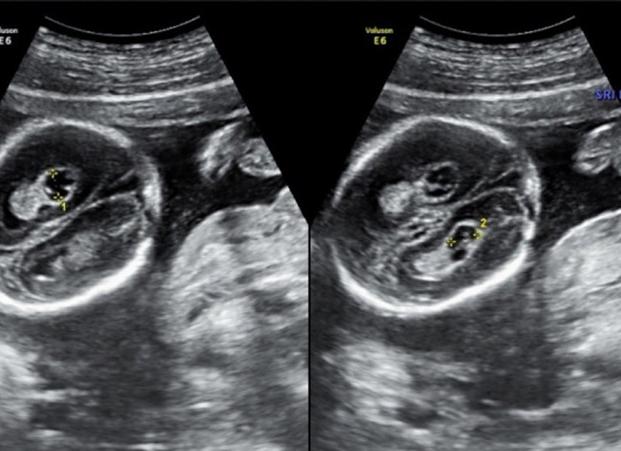

Кисты сосудистых сплетений у плода чаще всего обнаруживаются во втором триместре беременности, во время планового УЗИ. Стоит отметить, что эти образования бывают единичными и множественными, односторонними и двусторонними.

Независимо от месторасположения, сосудистые кисты в сплетениях сосудов плода можно обнаружить с помощью УЗИ на 18 неделе у 1-3% женщин, вынашиваемых ребенка. В большинстве случаев где-то к 24-28 неделе беременности образовавшиеся кисты рассасываются, поэтому на развитие мозга они никак не влияют, так как он начинает формироваться лишь на 24-й неделе развития плода.

Обычно кисты сосудистых сплетений у плода выявляют на 18–22 неделях беременности при проведении планового ультразвукового исследования. Многие будущие мамы, услышав такой диагноз, сильно пугаются и принимают его за патологию головного мозга. Однако наличие такой кисты у плода в подавляющем большинстве случаев не представляет никакой опасности. Рассмотрим, что представляет собой киста головного мозга у плода, по каким причинам она формируется и какое лечение необходимо в таких случаях.

Сосудистые сплетения являются одной из первых структур головного мозга, которые формируются у плода. Они представляют собой сеть мелких сосудов, которые вырабатывают жидкость, питающую головной и спинной мозг. Если внутри сосудистых сплетений скапливается слишком большое количество мозговой жидкости, на сосудах образуется мелкий пузырек, который при УЗИ диагностируется как киста.

Подобного рода кисты могут быть единичными или множественными, односторонними или двусторонними. Точные причины их образования в настоящее время не установлены, но считается, что спровоцировать развитие кисты у плода могут такие факторы, как острые инфекционные и вирусные заболевания у матери или неправильное положение плода, которое приводит к нарушению кровотока. Но некоторые специалисты считают, что формирование таких кист у плода является всего лишь одним из этапов внутриутробного развития.